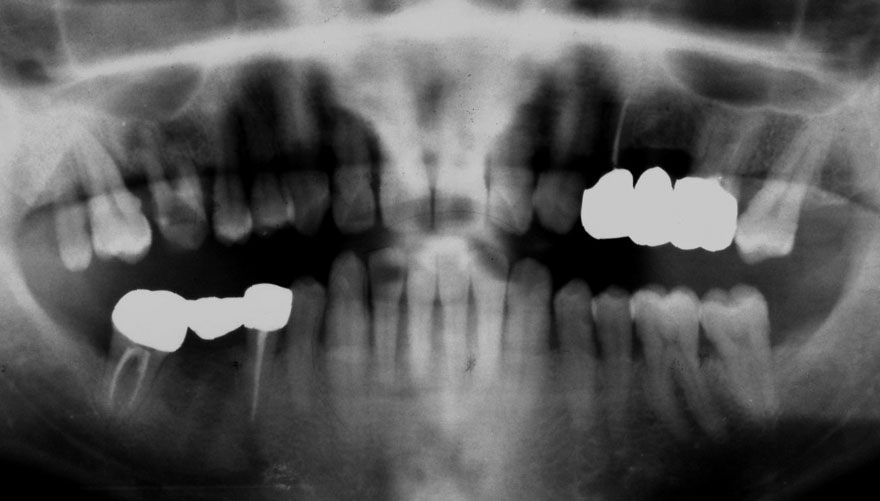

初診時 39歳 女性 平均歯槽骨喪失量:1.82mm

29年後 68歳

平均歯槽骨喪失量:2.21mm

29年間喪失量:-0.39mm

年間喪失速度:-0.013mm

(ケア頻度:5.55ヵ月ごと)